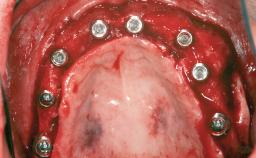

A 47-year-old Caucasian woman with a single-tooth edentulous space at the site of the left maxillary canine was referred for treatment. She had undergone traumatic extraction of this impacted canine several months before referral. Her chief complaint was the dissatisfying appearance of her smile. The patient desired a stable and esthetic rehabilitation of the site. Her dental history showed no evidence of periodontal disease or bruxism. She had no systemic diseases, was not taking any medications, and did not smoke. The extraoral examination revealed a high lip line and an inadequate soft-tissue volume at the defective canine site. Large black triangles were visible between the canine and its adjacent teeth.

Bone Augmentation Staged|Vertical

Augmentation Materials Autogenous chips|Membrane

Soft Tissue Grafting Simultaneous